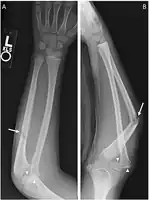

Monteggia fracture dislocation

There are four types (depending upon displacement of the radial head):[3]

- I - Extension type (60%) - ulna shaft angulates anteriorly (extends) and radial head dislocates anteriorly.

- II - Flexion type (15%) - ulna shaft angulates posteriorly (flexes) and radial head dislocates posteriorly.

- III - Lateral type (20%) - ulna shaft angulates laterally (bent to outside) and radial head dislocates to the side.

- IV - Combined type (5%) - ulna shaft and radial shaft are both fractured and radial head is dislocated, typically anteriorly.